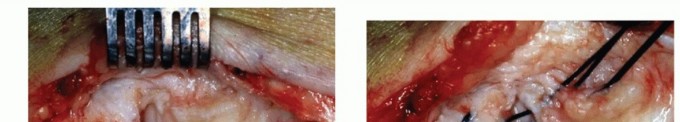

- Complete Acute Rupture

Because the rupture is mostly situated at the proximal end of the deltoid ligament (TECH FIG 3),

reattachment to the medial malleolus is achieved by interosseous sutures; a bony anchor can also be used for refixation to the bone.6 - Chronic Rupture of the Superficial Deltoid Ligament

- TECH FIG 3 • Acute deltoid rupture. This 28-year-old soccer player sustained a valgus trauma, causing an acute giving way of the foot. A. MR imaging reveals complete disruption of the ligament close to its proximal insertion to the medial malleolus. B. Surgical exploration confirms complete disruption of the deltoid ligament, although the posterior tibial tendon remained intact.